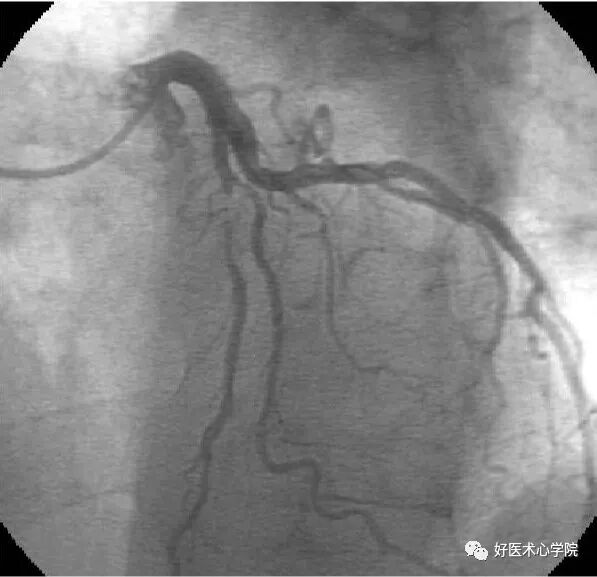

左前斜位:观察右冠全长,但难以看到远段分叉。

此时可以加足位可以观察。

造影导丝是什么珍藏 冠脉造影从流程到诊断,基础必备!_https://www.jmylbn.com_新闻资讯_第53张

△左前斜位下的右冠